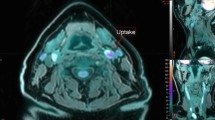

We performed a direct comparison of 18F-FOL and 18F-FDG in vivo PET/CT imaging of atherosclerotic aorta in Watanabe rabbits. Our results revealed a rapid clearance of 18F-FOL from circulating blood, and a comparable maximum TBR (SUVmax, aorta/SUVmean, blood) in the atherosclerotic aorta to that of 18F-FDG (Fig. 5). There was a high association between the maximum TBR of 18F-FOL PET and the areal percentage of RAM-11-positive staining of macrophages (linear mixed model P = 0.0031) in the corresponding segment of the aorta (Fig. 6A). Furthermore, there was an association between maximum TBR obtained with 18F-FOL and 18F-FDG PET (linear mixed model P = 0.0088) in the same segments of the aorta (Fig. 6B). The average uptake of 18F-FOL (2.6) in the whole aorta was similar to that of 18F-FDG (1.9; P = 0.074; Table 3).

18F-FOL PET/CT imaging of rabbits. (A) Representative coronal views of in vivo PET/CT images of a rabbit (3.4 kg, tracer doses 40 MBq/kg) with 18F-FOL (88–90 min post-injection) and 18F-FDG (170–180 min post-injection). White arrows denote a segment with advanced atherosclerosis in the abdominal aorta, with an 18F-FOL maximum target-to-background ratio (TBR = maximum standardized uptake value (SUV) of aorta divided by mean SUV of blood as determined from the inferior vena cava, SUVmax, aorta/SUVmean, blood) of 6.0 and an 18F-FDG maximum TBR of 2.4. Enlarged coronal PET/CT images of the aorta are shown in the right panels. Blue arrows denote aorta with lower tracer uptake. PET images are displayed in the same color scale. (B) Representative 18F-FOL time-activity curves of plaque (white arrow in Figure A) and blood. (C) Distribution kinetics of 18F-FOL in the selected organs (mean ± SD, n = 4).